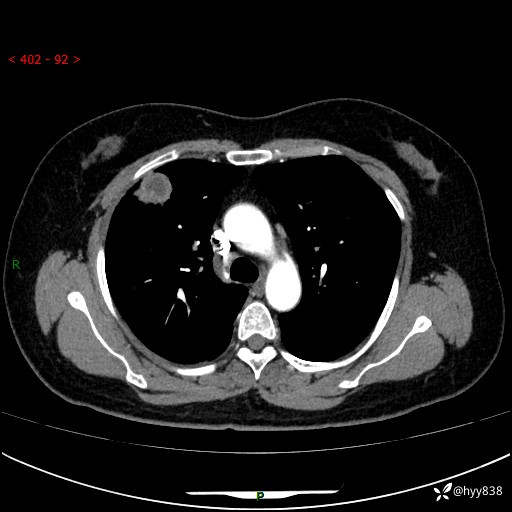

现病史:患者于2天余前无明显出现间断胸痛,无头痛、头晕,无心慌、胸闷、胸痛、呼吸困难、低热、盗汗,无腹痛、腹胀等不适,未进行进一步诊治。于2024.04.14在当地市人民医院行胸部CT检查提示:右肺上叶胸膜下结节。现患者为求进一步诊治,来我院就诊。以“肺肿物”收入我科。 患者自起病以来,精神可,睡眠可,饮食可,大小便正常,体重无明显改变。

胸部CT增强(肺窗,外院平扫)